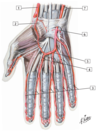

1 - Lumbrical muscle in its fascial sheath

2 - Flexor tendons to 5th digit in common flexor sheath (ulnar bursa)

3 - Hypothenar muscles

4 - Dorsal interosseous muscles

5 - Palmar interosseous muscles

6 - Adductor pollicis muscle

7 - Profundus and superficialis flexor tendons to 3rd digit